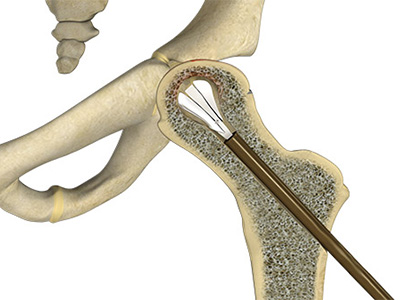

Osteoarthritis of the Hip Avascular Necrosis

Avascular Necrosis Borderline Hip Dysplasia